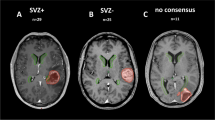

This study was approved by the Institutional Review Board and Ethics Committee (No. S-056/2015) and retrospectively evaluated 54 isocitrate dehydrogenase-1 (IDH1) wild-type GBMs with available tissue samples that completed a course of radiotherapy (RT) in the Department of Radiation Oncology at University Hospital Heidelberg from 2005–2013. Of these patients, radiographic assessment using magnetic resonance imaging (MRI) was conducted for stratification into two cohorts (SVZ– and SVZ+). The latter (also labeled as “central” GBMs) was defined by the contrast-enhanced lesion having infiltrated the borders of the lateral ventricle and SVZ (5 mm margin lateral to the lateral ventricles), which could be accompanied by subependymal spreading (tumor-related contrast enhancement spreading along the ventricle walls). The remainders were categorized as SVZ–, or “peripheral” GBMs. The SVZ– patients were matched with the SVZ+ patients according to tumor localization, performance status, age, availability of sufficient pre-radiotherapeutic tumor tissue samples, and follow-up data.

Subventricular zone positive “central” (SVZ+) and subventricular zone negative “peripheral” (SVZ–) glioblastoma differ in their epigenomic signatures. a Imaging-based (MRI) classification of GBM patients with poor prognosis SVZ+ tumors (Kaplan–Meier, Cox model likelihood ratio test, LRT). b Identification of SVZ specific DNA methylome signature (SVZM) consisting of 15 CpGs. Left: random forest derived rank order of single CpGs according to their relevance to differentiate SVZ state are shown (left red dots, right CpG annotations and importance score). c SVZM Classification separates the training cohort into two main clusters (heatmap, hcl with Euclidean distance and complete linkage). Molecular (MGMT, G-CIMP) and MRI classifications are also provided. An inferior prognosis of GBM patients with SVZM+ tumors was found by Kaplan–Meier analysis of patient survival

As compared to MRI-based classification, eight (14.8%) tumors were reclassified following molecular SVZM assessment. Interestingly, SVZM was able to separate these patients into two distinct prognostic subgroups confirmed on survival analysis (p = 0.02 by Weibull distribution, Fig. 2A, updated survival data after extended follow-up). Representative MRI images of tumors with mismatching radiographic and molecular classifications illustrate current difficulties associated with discrimination of SVZ-driven central GBM from secondary infiltration of peripheral tumors into the SVZ. Most MRI SVZ-/SVZM + tumors showed FLAIR signal reaching the SVZ (Fig. 2B, Suppl. Figure 13, online resource). FLAIR signal for classification, however, is only useful if the SVZ region is not reached (Suppl. Figure 14, online resource).

Discordance between SVZM vs. MRI-based classifications. a Overall survival of all differently assigned patients indicating an inferior outcome in patients with SVZM+ but according to MRI SVZ negative tumors. Kaplan–Meier curves and parametric survival model (Weibull distribution, dashed line, LRT). b Tumor localization of representative patients with discordant classification highlights the difficulty to distinguish between secondary invasion to the SVZ region and tumors originating from this region solely by the imaging method. c A significantly increased hazard ratio (HR: 2.48, p < 0.004) for SVZM by univariable survival analysis (Cox model) versus other parameter including classifications based on MRI SVZ+ vs SVZ–; female vs male; performance status (KPS ≥ 80 vs < 80); multi- vs unifocal presentation; chemotherapy (TMZ: adjuvant/concurrent vs. incomplete treatment); radiation dose (≥ 60 Gy vs < 60 Gy), surgery: subtotal vs total and MGMT status

Performance of SVZM vs. MRI in the validation cohort. a Overview of multiple layer of data that were correlated with the SVZM state in training/validation cohorts. Methylome and copy number variation (CNV) analysis by 450 K microarrays, T1 contrast enhanced (CE) MRI, mutational profile by whole exome sequencing (WXS), deep “panel” NGS and RNAseq. b SVZ± assignment of the validation cohort by cluster analysis of the 15 CpG signature (maximum distance, ward.D) and prognostic evaluation (Kaplan–Meier, Cox model, and LRT). c Heterogeneity of SVZ classification by MRI in the validation cohort. Manual rating of patients to SVZ classes based on MRI shows discordance between the three observations for a fraction of patients (intraclass correlation, ICC). Comparative univariable survival analyses (bottom) for the 24 most consistently rated tumors by MRI vs. SVZM (Cox model)